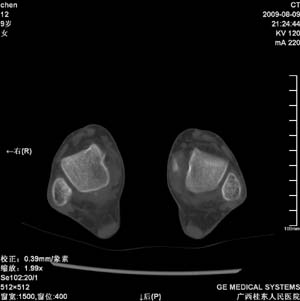

标题: PED2867:右侧内踝肿胀,骨质改变,请各位老师会诊 [打印本页]

标题: PED2867:右侧内踝肿胀,骨质改变,请各位老师会诊

九岁小朋友,近期左侧内踝疼痛,局部肿胀,平时无特殊,近期经常溜干冰

对不起,是右侧内踝肿胀

双侧踝关节骨质及关节结构均未见明显异常。考虑玩多了累的,休息休息看看吧!

骨质及关节结构未见异常。